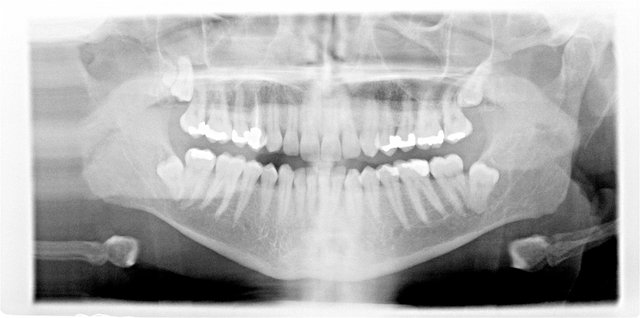

Orthopantomographie (OPT)

Tiefe Karies im oberen Weisheitszahn

Verlagerung der Weisheitszähne

Follikuläre Zysten um die unteren beiden Weisheitszähne